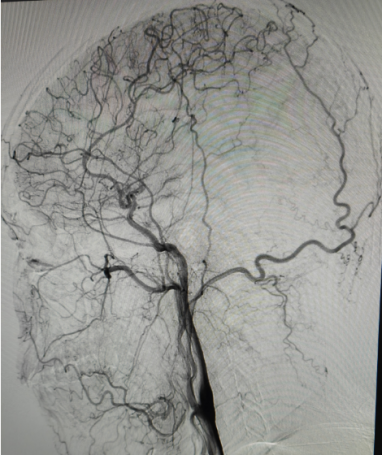

术中所见:

左侧大脑中动脉近端闭塞,新生血管形成呈烟雾状,由左侧大脑前动脉及大脑后动脉经脑膜支代偿。

右侧大脑后动脉重度狭窄。

结合造影表现,患者右侧大脑中动脉闭塞代偿较完全,左侧大脑后动脉重度狭窄,给予患者制定合适治疗方案,预防卒中再次发生。